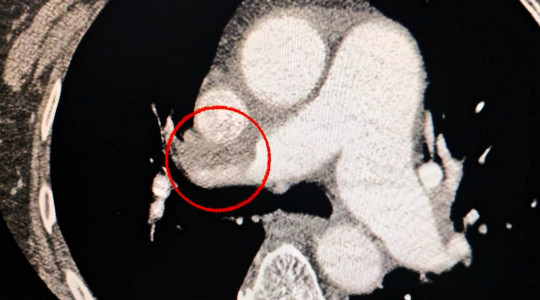

Жительку Одеси доставили до медзакладу у важкому стані з ознаками гострого порушення мозкового кровообігу. Під час комп’ютерної томографії фахівці виявили оклюзію середньої мозкової артерії.

Окрім цього, лікарів насторожили скарги пацієнтки на утруднене дихання. Додаткове обстеження легенів підтвердило ще один небезпечний діагноз — тромбоемболію легеневої артерії.